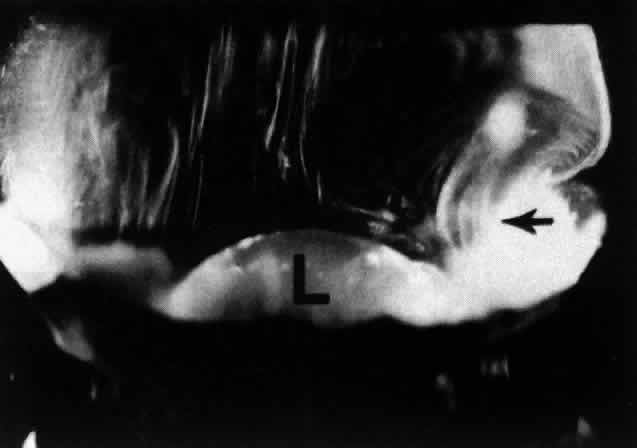

Fig. 9. This view of the posterior and central vitreous from a 4-year-old child demonstrates a dense vitreous cortex (arrows) with hyalocytes (small retractile “spots” in cortex) and no intravitreal fibrous structures. The lens (L) is seen below.

During childhood only the vitreous cortex scatters incident light and thus appears dense (Fig. 9). There are no visible fibers within the corpus vitreous until middle age (see Figs. 4 THROUGH 6). During old age these fibers become thickened and tortuous, associated with many pockets of liquid vitreous and a collapsed (syneretic) appearance (Fig. 10). These changes are the result of age-related biochemical alterations in the composition and organization of the molecular components that simultaneously result in vitreous liquefaction and fiber formation. Pockets of liquid vitreous have classically been called “lacunae.” In addition to having a low density of collagen during youth, the central vitreous is the first region to undergo liquefaction during middle age.16 A report by Kishi and Shimizu18 described the presence of a “posterior vitreous pocket” that the authors interpreted to represent an anatomic entity. However, over 95% of the eyes examined in that study were from persons aged 65 years or older. Thus, these findings represent the result of age-related vitreous liquefaction in the central precortical posterior vitreous.93 Such changes could also explain the preferential pooling of aqueous dyes such as India ink17 placed onto the anterior vitreous and allowed to collect anterior to the macula in what appears as a “bursa.”17,94,95 The use of fluorescein by Kishi and Shimizu18 represents but another way of demonstrating the phenomenon of vitreous liquefaction in this region.